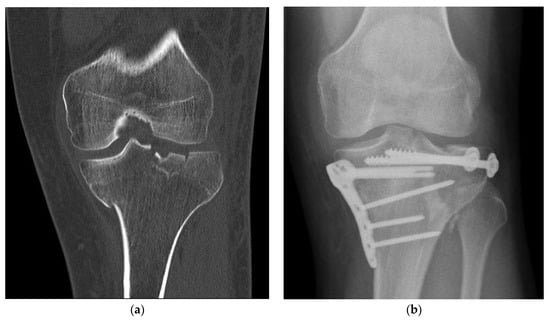

An important criterion in clinical evaluation after surgery is the survey of complications (Table 1). There was no relevant difference between the BSM and the ED group. Complications were noticed in the BSM (n = 21, 34.4%) and ED (n = 23, 51.1%) groups (p = 0.11). Regarding the number of complications, a wider range with a non-significant difference (p = 0.07) was seen in the BSM group [0.0:4.0; 0.43 ± 0.72] compared with the ED group [0.0:2.0; 0.64 ± 0.71]. Pseudarthrosis decreased in the BSM group (n = 3, 4.9%) compared with the ED group (n = 7, 15.6%) nonsignificant (p = 0.09) (Figure 3). Delayed healing, ligamentous and muscular damage, complex regional pain syndrome (CRPS), previous death before follow-up, secondary diseases and neurological diseases showed no significant difference (p > 0.05). In the evaluation for the risk of using bone substitute materials, infections were detected in the ED (n = 1, 2.2%) and BSM groups (n = 2, 3.3%). When comparing mal-union in the BSM and ED groups, a non-significant difference was found (p = 0.07). When summarizing the significance of complications, no difference was found. In the clinic, relative (RR) and absolute risk (AR) reductions of complications allow the use of new therapies. Bone graft augmentation resulted in an RR of 32.64%, an ARR of 16.68%, and an NNT of 5.99.

Figure 3. Severe complication, pseudarthrosis, resulting from a proximal humeral fracture, resulted by empty defect treatment. (a) Preoperative 3D CT reconstruction showed a sub-capital humeral fracture; (b) post-surgical care radiograph examination demonstrated an atrophic nonunion. Furthermore, two screws of the humeral head were broken.